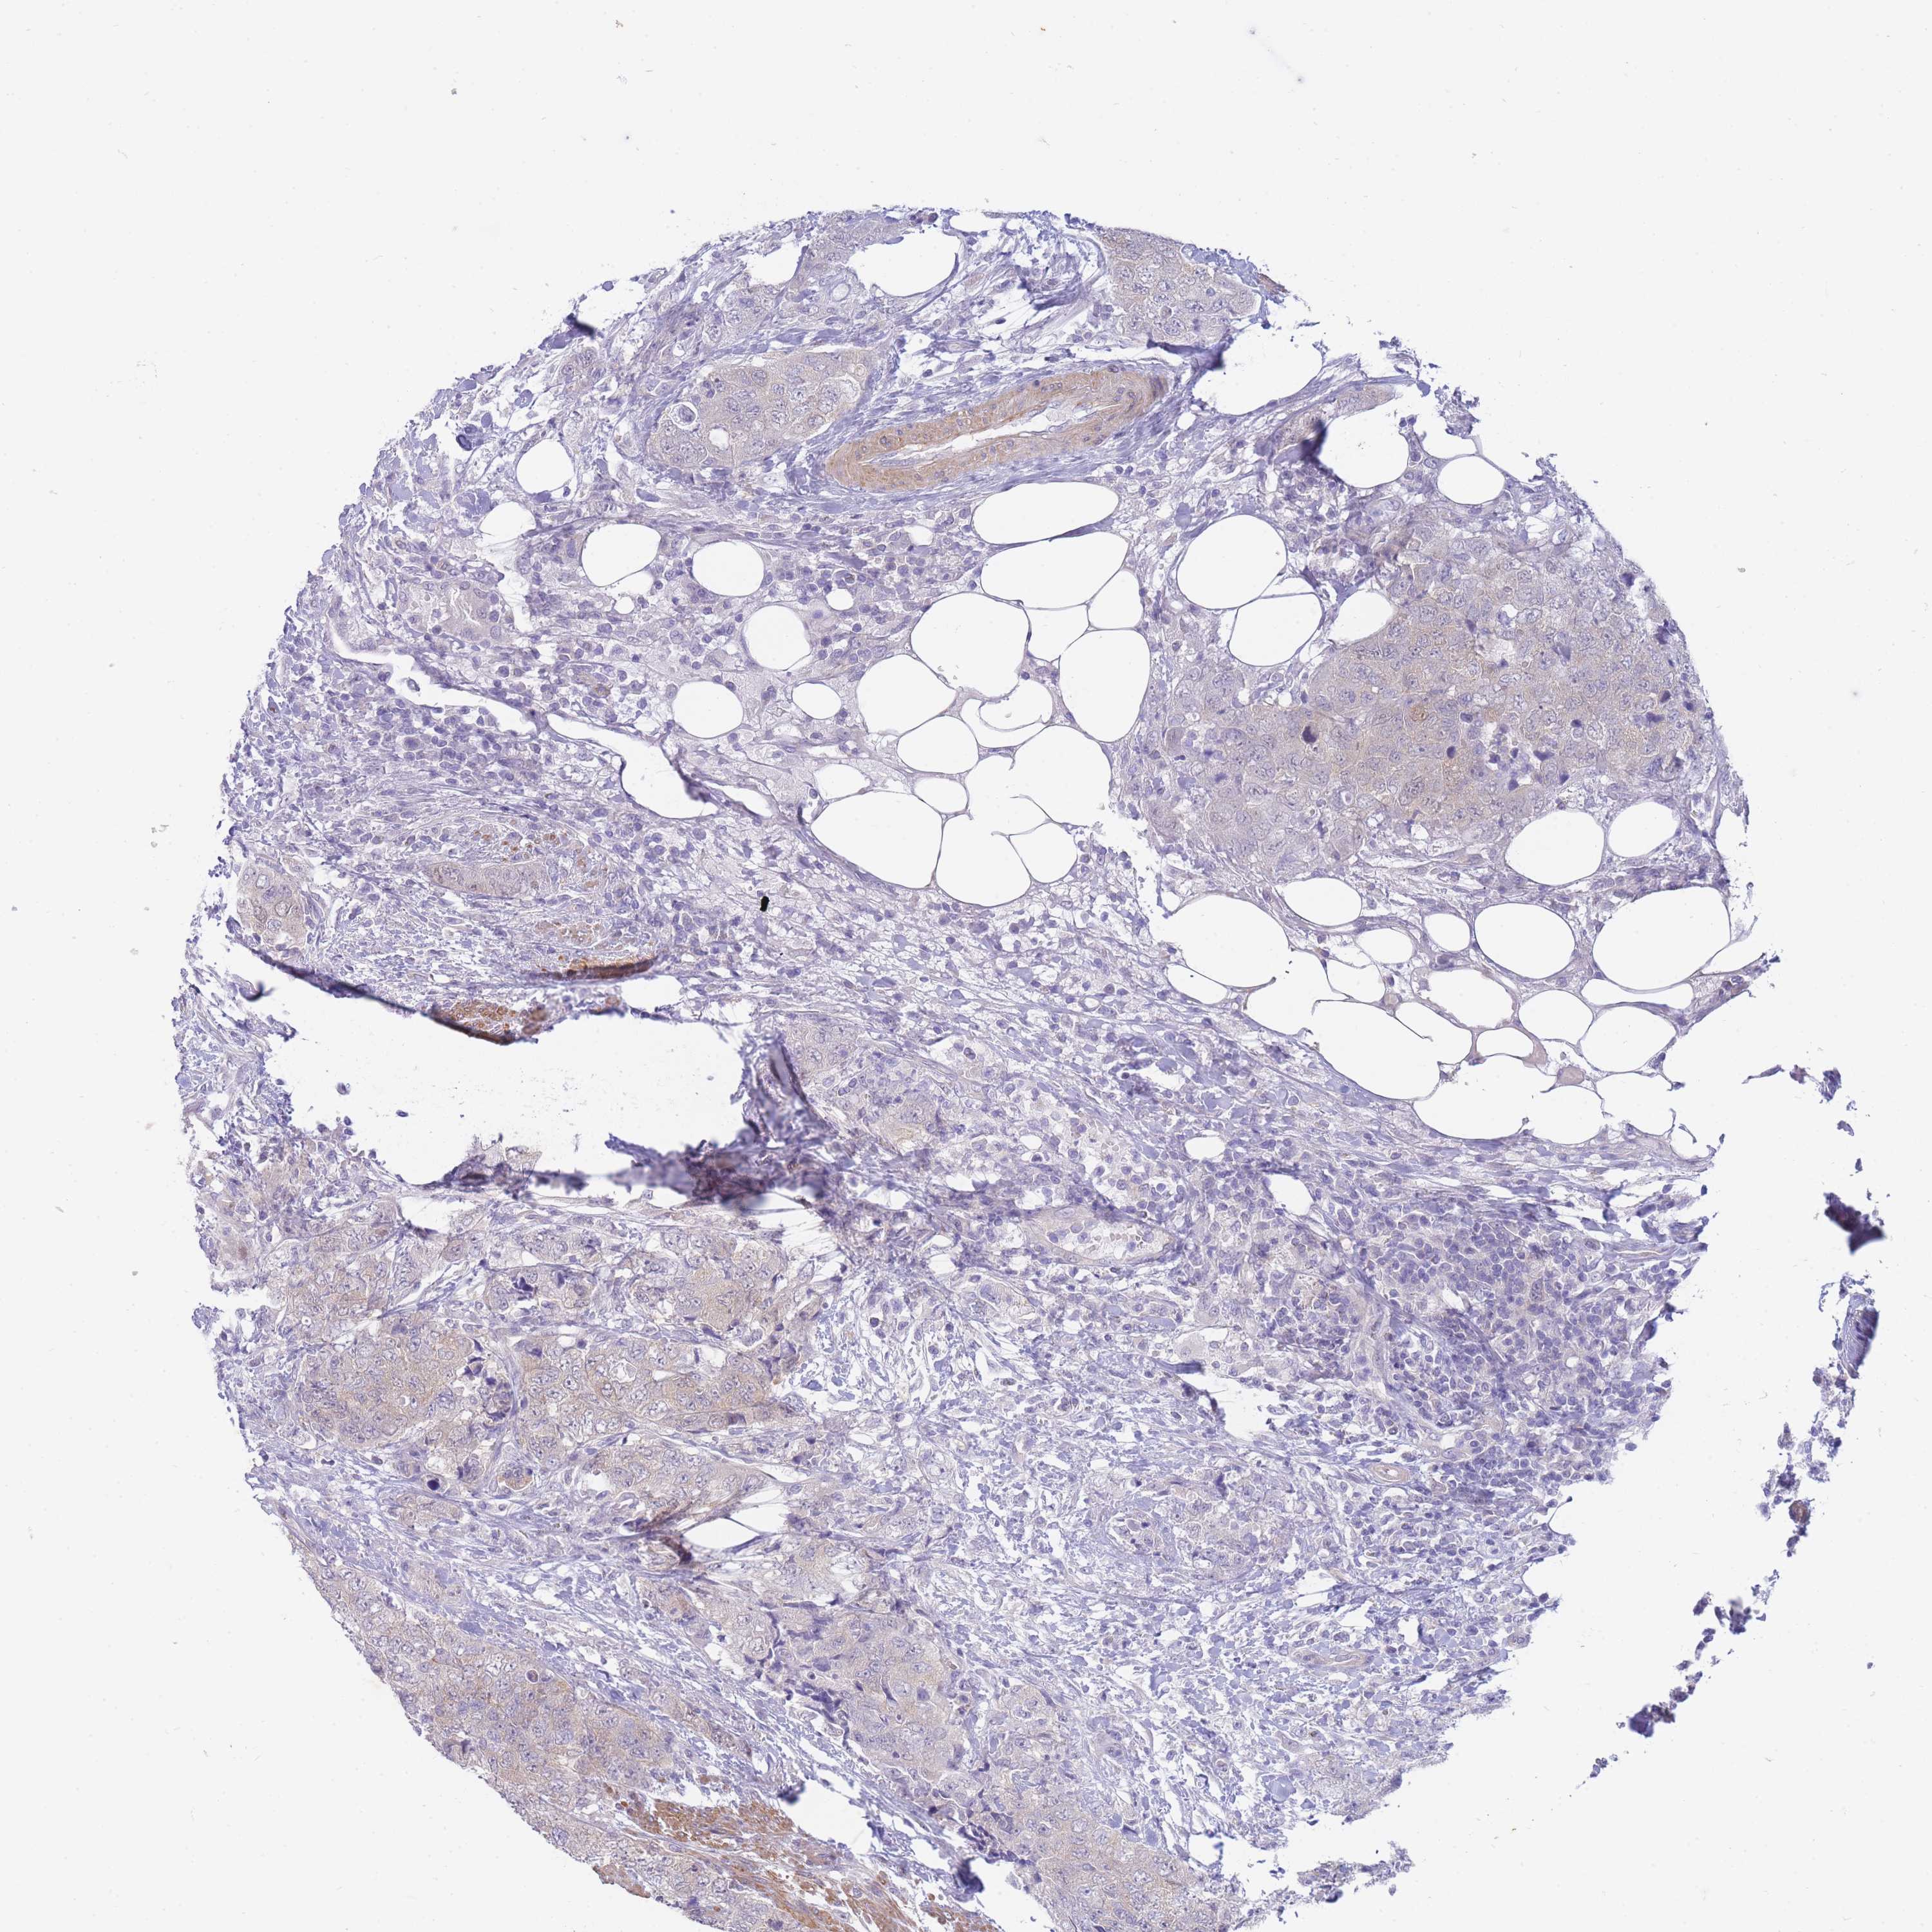

UROTHELIAL CANCER - Protein expressioni

A mouse-over function shows sample information and annotation data. Click on an image to view it in a full screen mode. Samples can be filtered based on level of antibody staining by selecting one or several of the following categories: high, medium, low and not detected. The assay and annotation is described here.

Note that samples used for immunohistochemistry by the Human Protein Atlas do not correspond to samples in the TCGA dataset.

Antibody stainingi

Antibody staining in the annotated cell types in the current human tissue is reported as not detected, low, medium, or high, based on conventional immunohistochemistry profiling in selected tissues. This score is based on the combination of the staining intensity and fraction of stained cells.

Each image is clickable and will lead to virtual microscopy that enables deeper exploration of all samples and also displays staining intensity scores, fraction scores and subcellular localization as well as patient and tissue information for each sample.

Antibody HPA043949

Antibody HPA069215

Antibody CAB015942

Staining

High

Medium

Low

Not detected

Intensity

Strong

Moderate

Weak

Negative

Quantity

>75%

75%-25%

<25%

None

Location

Nuclear

Cytoplasmic/membranous

Cytoplasmic/membranous,nuclear

Urothelial carcinoma, High grade

Urothelial carcinoma, Low grade